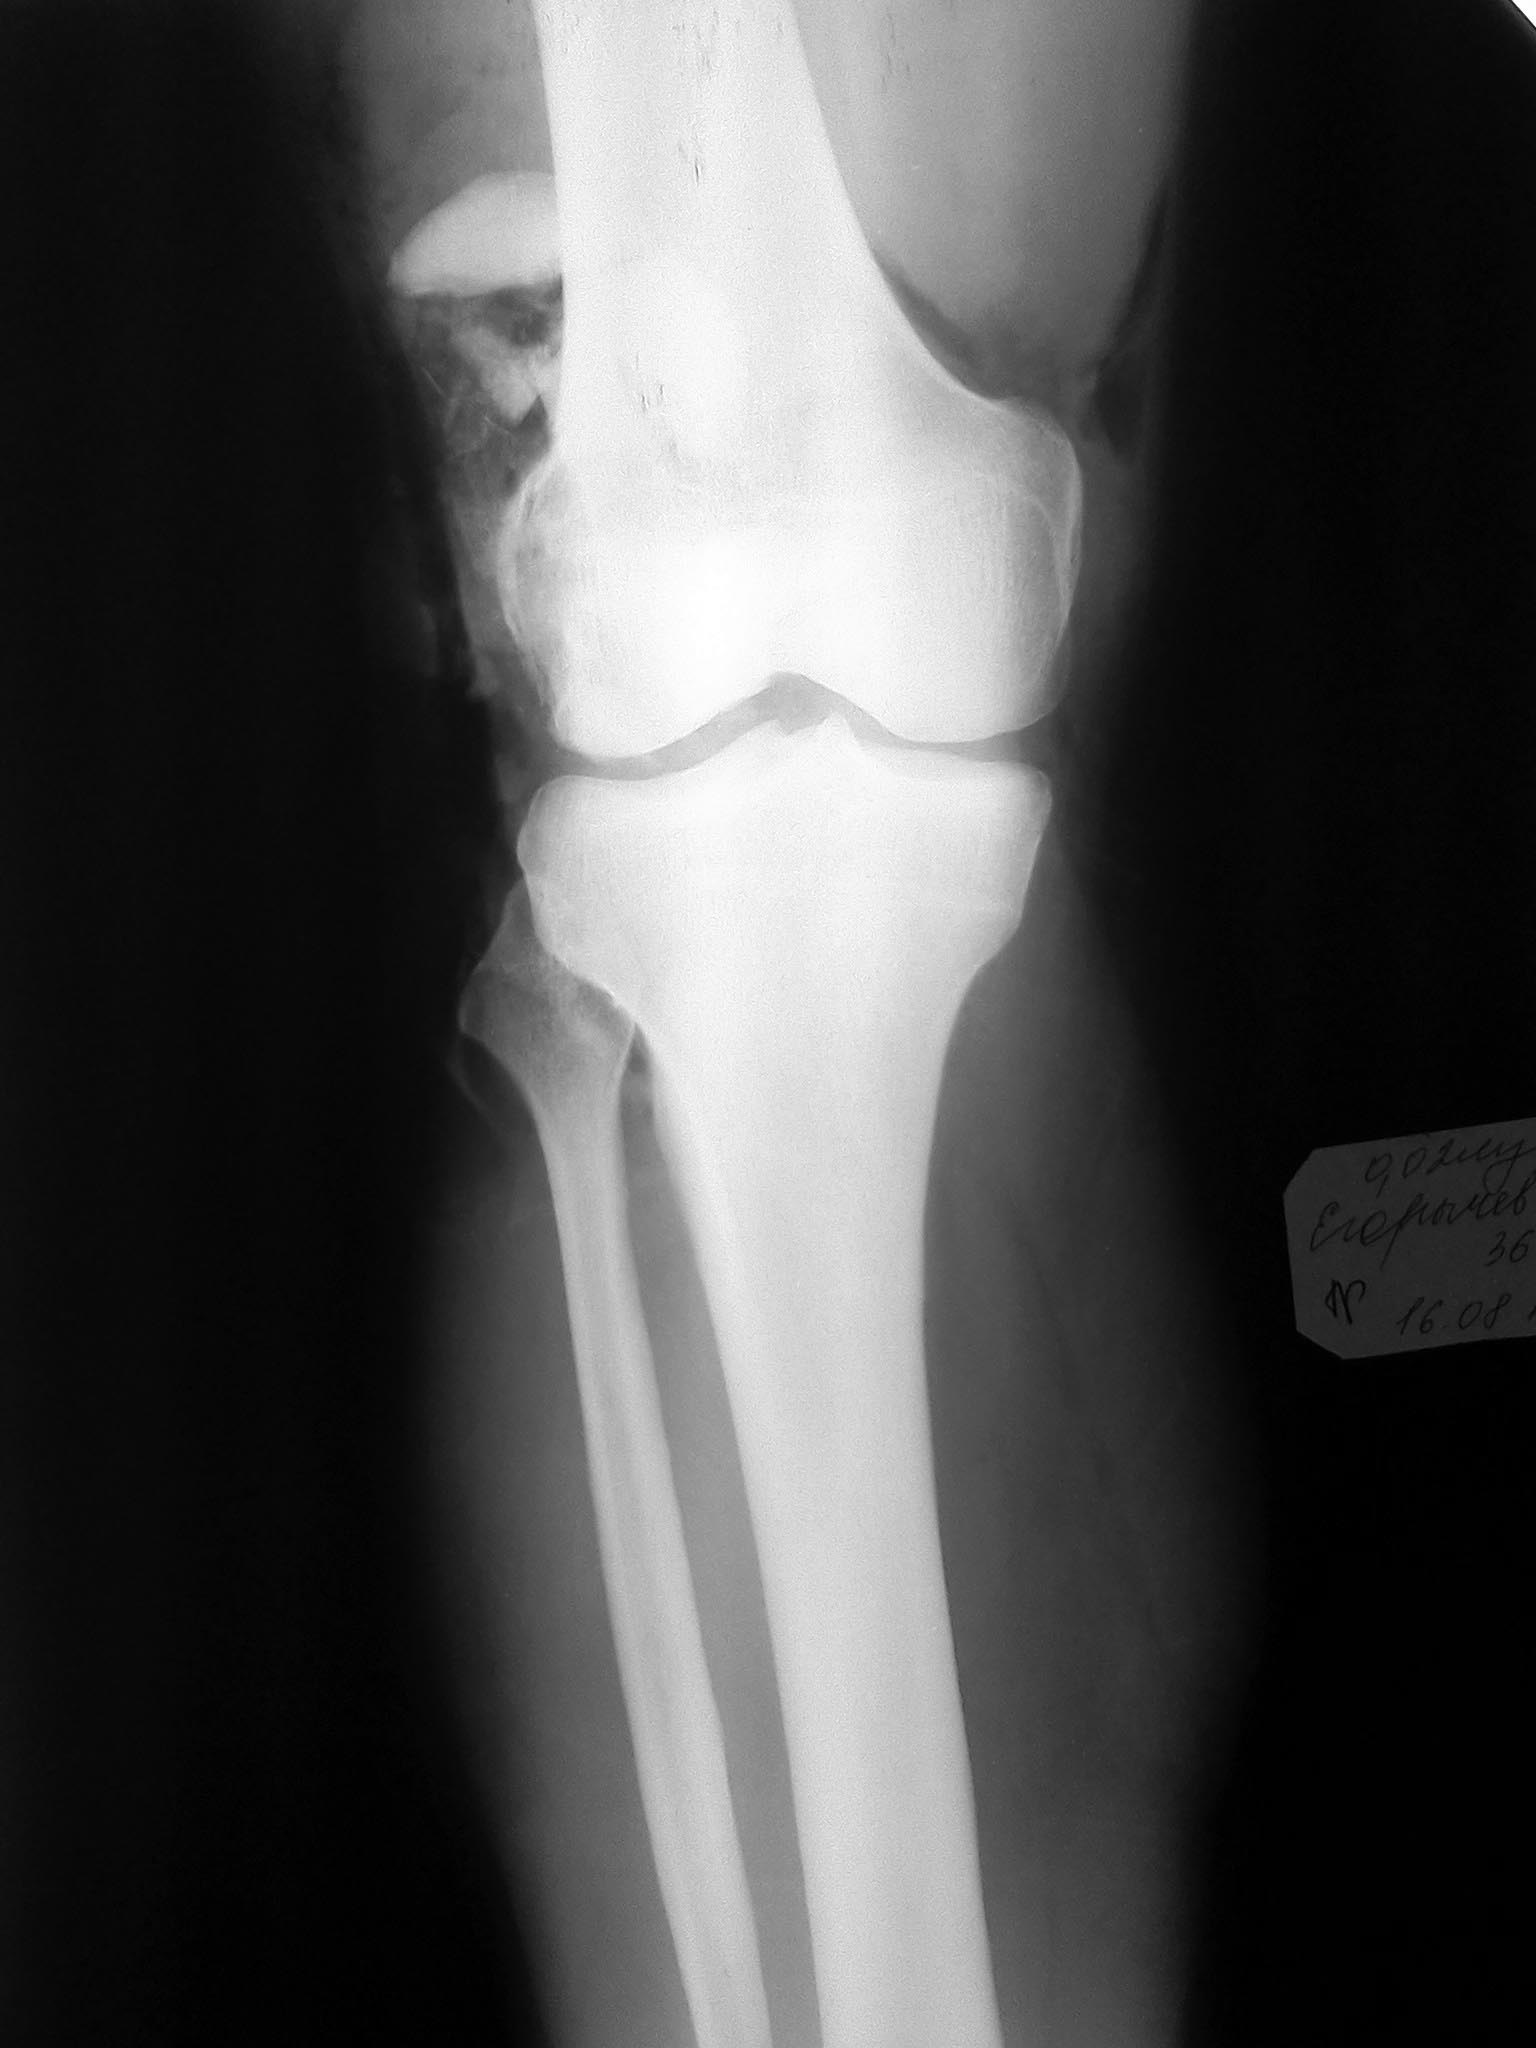

Вложение не в текстовом формате было извлечено…

Имя     : IMG685.jpg

Тип     : image/jpeg

Размер  : 97296 байтов

Описание: отсутствует

Url     : http://weborto.net:8080/pipermail/ortho/attachments/20130819/c355101e/attachment-0004.jpg